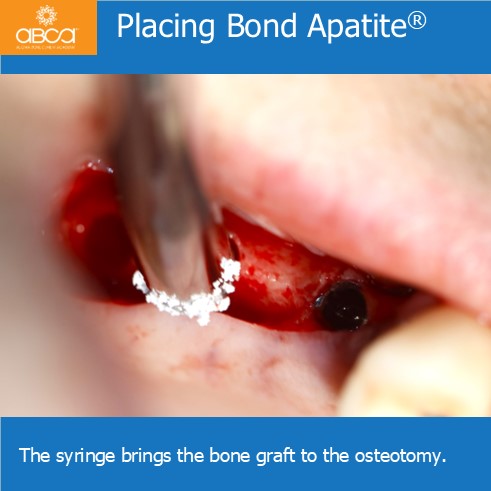

The patient is a 50 year old female with severe posterior maxillary atrophy. She came in for a posterior maxillary implant procedure. Implants were placed using Augma Lift™ Kit B.

Sinus lift with Augma Lift™ Kit B with 4-5 mm sub sinus bone height.

Sinus lift with Augma Lift™ Kit B with 4-5 mm sub sinus bone height. A young woman came to replace the missing first maxillary molar with moderate atrophy.

Sinus lift with Augma Lift™ Kit B in a case with 5 mm sub sinus bone height.

Sinus lift with Augma Lift™ Kit B in a case with 5 mm sub sinus bone height. The patient came for implant treatment in the region of teeth #16 (3)…

Sinus lift with Augma Lift™ Kit B in a case with missing teeth #14 (5), #15 (4), #16 (3), #17 (2) and a sub sinus bone height of 6 mm.

Sinus lift with Augma Lift™ Kit B in a case with 6 mm sub sinus bone height.